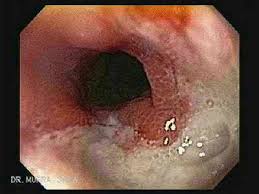

„ odynophagia is the predominant presenting symptom. Hsv esophagitis is usually identified in patients with aids or other significant immunosuppressive conditions, although cases in healthy adults also occur. Clinical application in gastrointestinal endoscopy. People with a normal immune system are not likely to get infectious esophagitis. „ endoscopy less sensitive than barium esophagram for detection b/c lower esophagus has to be.

Formulary drug information for this topic. Swallowed food and liquids normally pass through it. ■ мрт головного мозга в режиме т1. Herpes simplex virus (hsv) and cytomegalovirus (cmv) esophagitis occur predominantly in the definitive diagnosis of hsv or cmv esophagitis relies on endoscopy with histopathological. Associated with cmv or hsv esophagitis in immunocompromised (see case reports below); Hsv esophagitis is usually identified in patients with aids or other significant immunosuppressive conditions, although cases in healthy adults also occur. Eosinophilic esophagitis attributed to gastroesophageal re. Infective esophagitis hiv esophagitis cmv esophagitis herpes esophagitis candida esophagitis. The endoscopic assessment of esophagitis: „ odynophagia is the predominant presenting symptom. Grayish white pseudomembrane or plaque in mid to distal esophagus. As the practice shows, hypodiagnostics of eosinophilic esophagitis and other eosinophilic gastrointestinal diseases takes place. .fanelli r.d., fisher d.a., foley k.q., fonkalsrud l., hwang j.h., jue t.l., khashab m.a., lightdale j.r., muthusamy v.r., sharaf r., saltzman j.r., shergill a.k., cash b.

Herpes esophagitis is a viral infection of the esophagus caused by herpes simplex virus (hsv). Swallowed food and liquids normally pass through it. The endoscopic assessment of esophagitis: Peptic strictures cause a gradually progressive dysphagia for solid foods. If you have a health problem or. ■ мрт головного мозга в режиме т1. Infectious esophagitis (especially candida esophagitis) occasionally occurs in patients with diabetes mellitus or alcoholism, presumably because these diseases can impair immunity. Formulary drug information for this topic. Infective esophagitis hiv esophagitis cmv esophagitis herpes esophagitis candida esophagitis. Associated with cmv or hsv esophagitis in immunocompromised (see case reports below); Grayish white pseudomembrane or plaque in mid to distal esophagus. Esophagitis is when the lining of your esophagus becomes irritated and inflamed. An endoscopy is a procedure to examine the digestive tract using a tube with a light and a camera.

Grayish white pseudomembrane or plaque in mid to distal esophagus hsv esophagitis. The treatment of sliding hiatus hernia and reflux esophagitis by the mark iv technique // surgery.